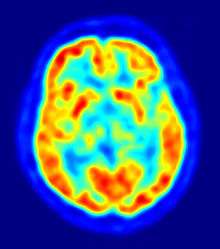

B. Localization of the area of significant brain volume reduction in initial PD compared with a group of participants without the disease in a neuroimaging study, which concluded that brainstem damage may be the first identifiable stage of PD neuropathology[56]

Computed tomography (CT) and conventional magnetic resonance imaging (MRI) brain scans of people with PD usually appear normal.[62] These techniques are nevertheless useful to rule out other diseases that can be secondary causes of parkinsonism, such as basal ganglia tumors, vascular pathology and hydrocephalus.[62] A specific technique of MRI, diffusion MRI, has been reported to be useful at discriminating between typical and atypical parkinsonism, although its exact diagnostic value is still under investigation.[62] Dopaminergic function in the basal ganglia can be measured with different PET and SPECT radioactive tracers. Examples are ioflupane (123I) (trade name DaTSCAN) and iometopane (Dopascan) for SPECT or fluorodeoxyglucose (18F)[62] and DTBZ[63] for PET. A pattern of reduced dopaminergic activity in the basal ganglia can aid in diagnosing PD.[62]